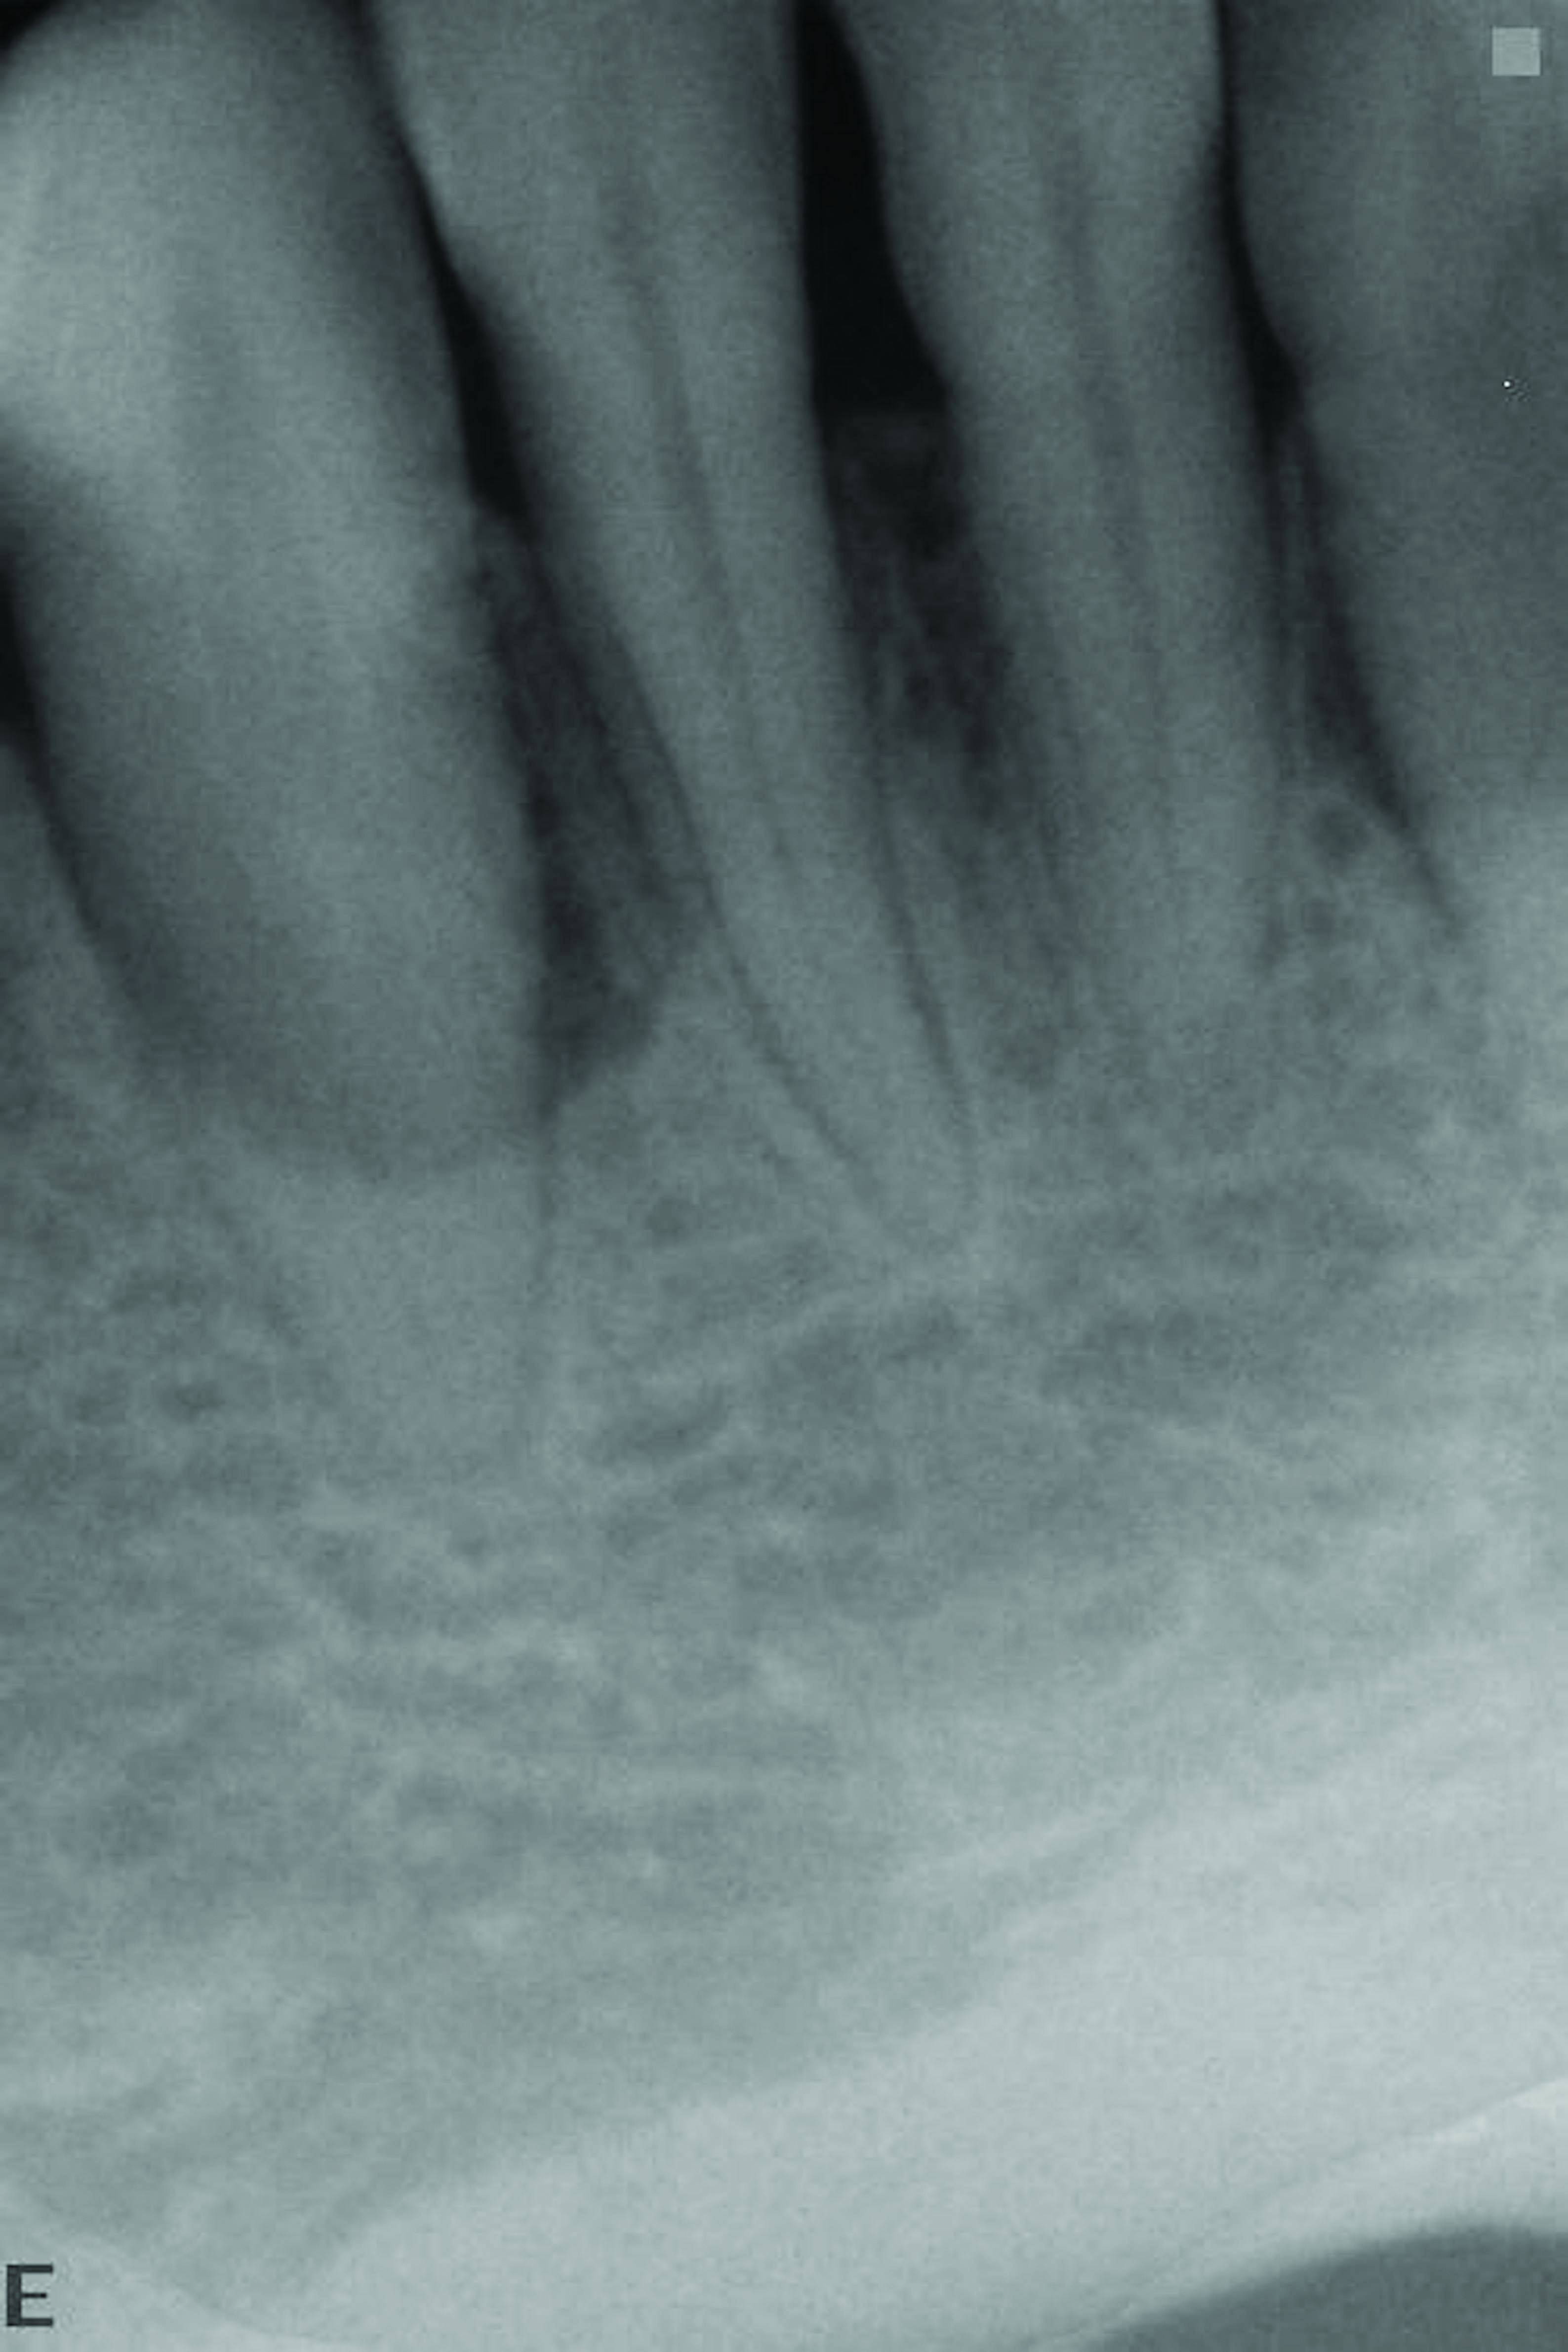

At the 13-month postoperative visit, the patient who had initially been referred for extraction and an implant still has the tooth with minimal probing depths and no mobility (Figure 20). She reported that she is happy that she did not have to have her canine extracted.

The 13-month postoperative radiograph. Significant regeneration is suggested.

Figure 20